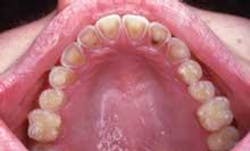

Intraoral examination revealed yellowish depressions on the lingual aspects of the maxillary teeth (see photo). The depressions appeared shallow, broad, smooth, and scooped out.

Another pattern of erosion that may occur presents as a smooth loss of enamel with exposure of dentin on the lingual surfaces of the maxillary teeth. If the lingual surface of the tooth is involved, a concave area of dentin surrounded by a thin, white line of enamel along the periphery of is seen. Chronic vomiting is associated with these characteristic changes of the lingual surfaces of the maxillary teeth. If the posterior teeth are involved, an extensive loss of enamel results on the occlusal surfaces. In posterior teeth with amalgam restorations, the edges of the restorations may extend above the level of the remaining tooth structure. Occasionally, entire cusps may be lost to erosion.